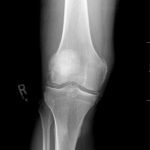

Radiographs of the knee showed multiple radio-dense lines paralleling the articular surface (see red arrows) consistent with calcium pyrophosphate crystal deposition within the joint often seen in calcium pyrophosphate disease (CPPD) also known as pseudogout.

Patients commonly present to the emergency department with non-traumatic joint pain. Arthrocentesis is an important diagnostic tool to evaluate for septic arthritis, gout, or pseudogout. Arthrocentesis can demonstrate crystals or abnormal cell count, gram stain, and culture.[1] In the evaluation of joint pain, plain films are usually obtained to evaluate for fracture, dislocation, effusion, or secondary signs of infection. In this case the classic x-ray supported the diagnosis of CPPD.2 The patient was found to have positively birefringent rhomboid shaped crystals consistent with pseudogout on arthrocentesis. Gram stain and culture were both negative. The patient was discharged with NSAIDs and had significant improvement in symptoms upon follow up with primary care physician in 3 days.